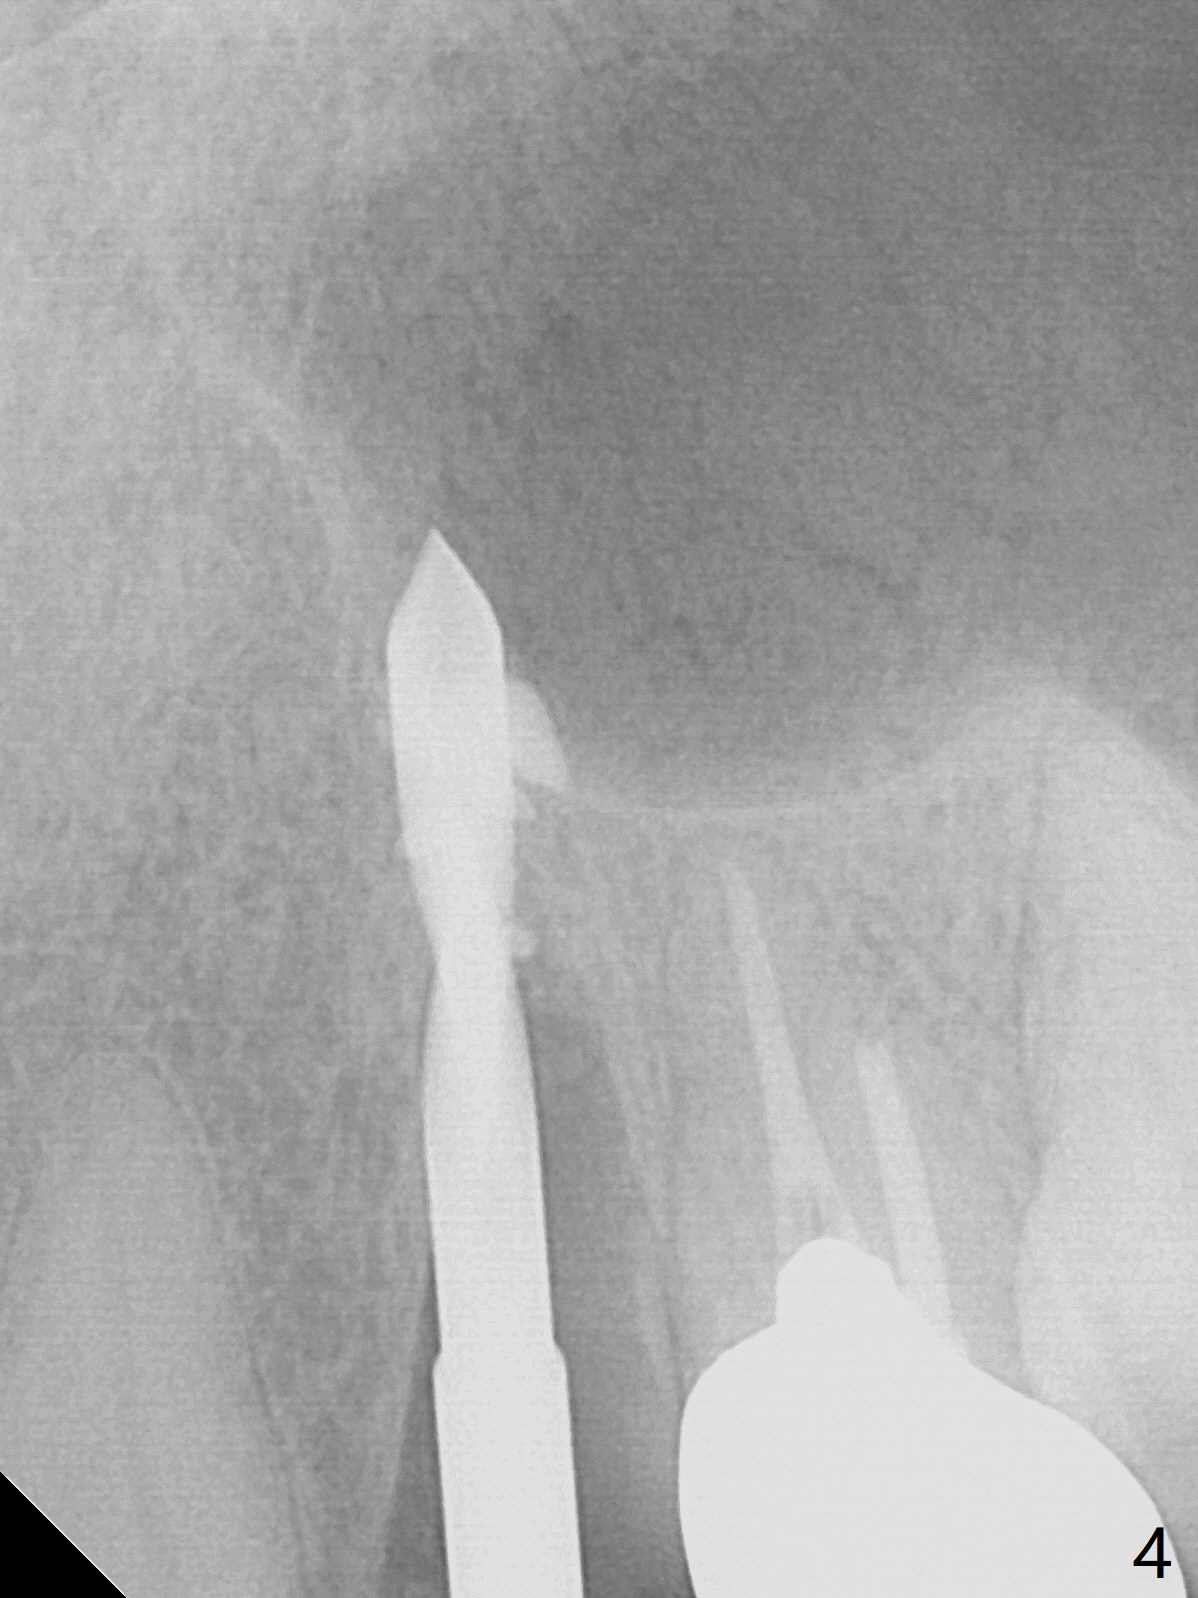

Extraction of the residual root at #11 (Fig.1) turns out to be difficult (Fig.2 (arrow: after use of small elevator). The tooth is sectioned (Fig.2 *); the palatal portion is removed, while the buccal one is trimmed until new moon-shaped and subgingival (Fig.3 * (gauze (G) packed in the socket while photo taking)). Initial osteotomy is 20 mm deep with nasal floor perforation (Fig.4). The subsequent depth is 17 mm (Fig.5). When a 5x17 mm tissue-level implant is placed (Fig.6,7; >60 Ncm), there is a gap between it and the socket shield (Fig.6 *). Gap-filling Vera Graft (Fig.8 *) also covers the shield prior to fabrication of an immediate provisional (Fig.9). There is no apparent bone loss 3.5 months postop (Fig.10). There is no buccal plate resorption 9 months postop (Fig.11). The implant is doing well 2 years postop (1 year 9 months post cementation, Fig.12).